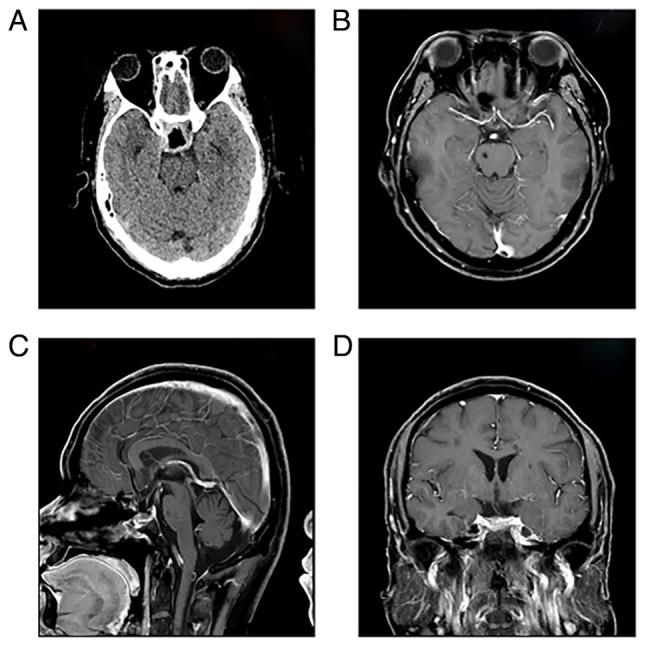

Pituitary apoplexy is a rare but life-threatening neurosurgical emergency, typically caused by acute hemorrhage or infarction of a pituitary adenoma within the sella turcica. It presents clinically with the sudden onset of severe headache, visual impairment and ophthalmoplegia. The present study reported the case of a 45-year-old male who experienced intermittent headaches and progressive right-sided visual deterioration over two months, with acute worsening in the preceding 6 h. The patient's medical history included coronary stent implantation and the patient had been on enteric-coated aspirin therapy for ~4 months. Magnetic resonance imaging and computed tomography of the head confirmed the diagnosis of pituitary apoplexy. The patient underwent emergency endoscopic transsphenoidal surgery, leading to significant improvement in right-sided vision. At the 6-month follow-up, the patient exhibited complete recovery with no evidence of tumor recurrence on imaging. This case highlights the importance of timely diagnosis and surgical intervention in achieving favorable outcomes in pituitary apoplexy and serves as a reminder for clinicians to consider the risk of hemorrhage in patients on long-term antiplatelet therapy.

垂体卒中是一种罕见但危及生命的神经外科急症,通常由蝶鞍内垂体腺瘤的急性出血或梗死引起。临床上表现为突发严重头痛、视力障碍和眼肌麻痹。本研究报告了一例45岁男性患者,该患者在两个月内经历了间歇性头痛和进行性右侧视力减退,并在之前6小时内急性加重。患者既往有冠状动脉支架植入史,服用肠溶阿司匹林治疗约4个月。头部磁共振成像和计算机断层扫描确诊为垂体卒中。患者接受了急诊内镜经蝶窦手术,右侧视力显著改善。在6个月的随访中,患者完全康复,影像学检查未发现肿瘤复发迹象。该病例强调了及时诊断和手术干预对于垂体卒中取得良好预后的重要性,并提醒临床医生考虑长期抗血小板治疗患者的出血风险。